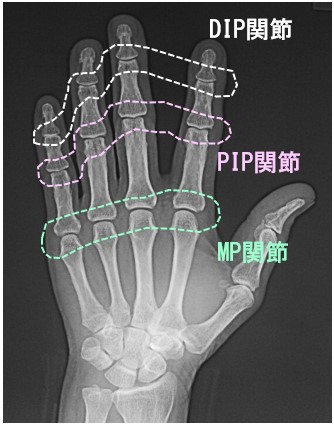

41才の医療従事者です。令和7年7月12日転倒して右小指から地面について、右小指PIP関節を脱臼し、自分で整復したそうです。当日当院を受診されました。脱臼は掌側に起きていたそうです。

41才女 Xp1.jpg

レントゲン像は、脱臼は整復されていて問題ありません。初診時、右小指は環指(薬指)とともに伸展位固定をしています。またボタン穴変形について、治りが悪い変形であることも説明しています。